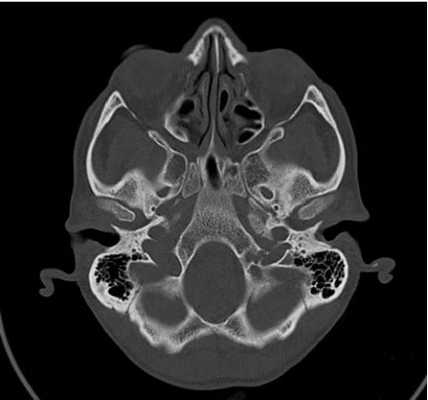

Что покажет КТ височных костей

Во время КТ получают послойные снимки височной кости и окружающих тканей в трех плоскостях. Толщина среза составляет всего несколько миллиметров, что позволяет врачу-рентгенологу рассмотреть не только все анатомические образования, но и минимальные патологические изменения.

На полученных снимках хорошо видны следующие структуры:

пирамида височной кости;

ячейки и антрум сосцевидного отростка;

улитка, преддверие, передний и задний полукружный каналы;

слуховые косточки среднего уха;

стенки наружного слухового прохода;

![Снимок (томограмма) височных костей в осевой проекции]()

Снимок (томограмма) височных костей в осевой проекции

С помощью КТ височных костей можно выявить любые заболевания воспалительного, травматического, опухолевого характера. Метод применяется для диагностики следующих патологий:

объемных образований, кист костной ткани и слухового аппарата;

воспалительных процессов (мастоидиты, отиты, остеомиелиты);

травматических повреждений (трещины, переломы);

дегенеративных изменений (отосклероз, дисплазия);

Большим преимуществом КТ перед другими диагностическими методами является возможность получения трехмерной модели височной кости. 3D-изображение необходимо перед хирургическим вмешательством, часто по поводу установки имплантата внутреннего уха, поскольку дает максимально четкое представление об особенностях анатомии у конкретного пациента.